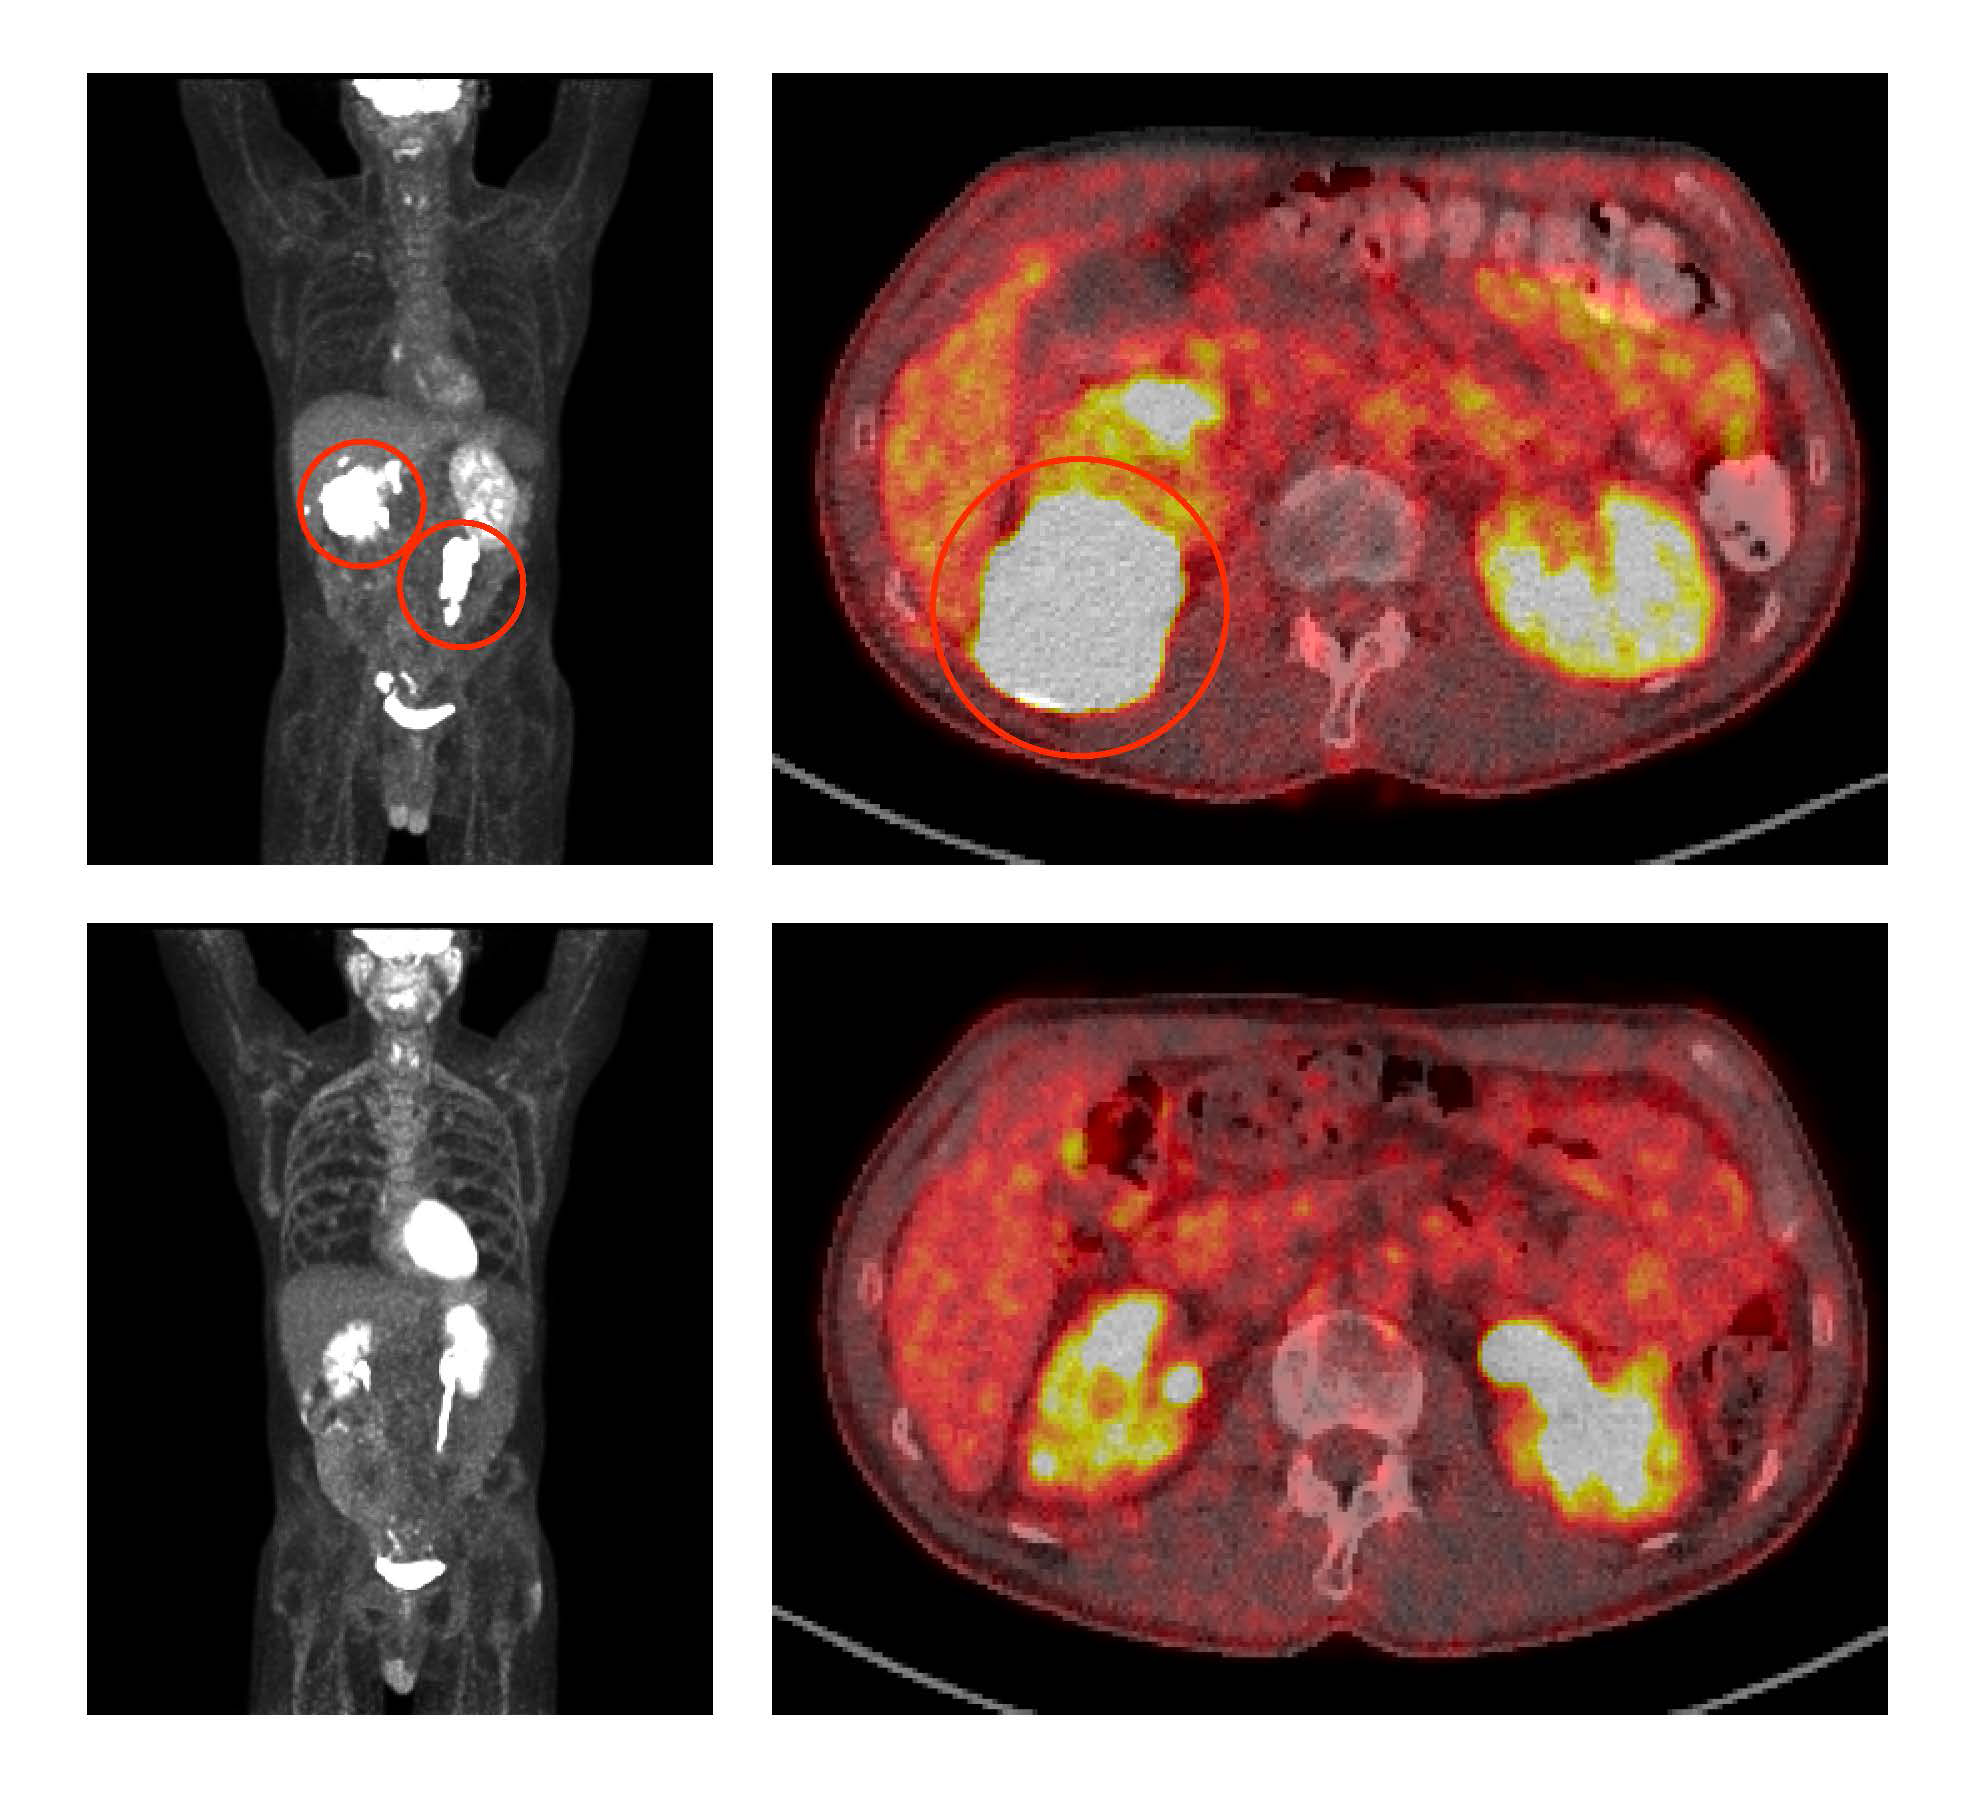

Researchers at the National Institutes of Health (NIH) have developed a non-chemotherapy treatment regimen that is achieving full remissions for some people with aggressive B-cell lymphoma that has come back or is no longer responding to standard treatments. The five-drug combination targets multiple molecular pathways that diffuse large B-cell lymphoma (DLBCL) tumors use to survive.

In a clinical trial at NIH’s National Cancer Institute, researchers tested the combination of venetoclax, ibrutinib, prednisone, obinutuzumab, and lenalidomide (called ViPOR) in 50 patients with DLBCL, the most common type of lymphoma. The treatment shrank tumors substantially in 26 of 48 (54%) evaluable patients, with 18 (38%) of those patients’ tumors disappearing entirely, known as a complete response. At two years, 36% of all patients were alive and 34% were free of disease. These benefits were seen mainly in people with two specific subtypes of DLBCL.

In the phase 1b/2 trial, 50 people with DLBCL that had relapsed or stopped responding to treatment were given six cycles of the ViPOR regimen. Responses to ViPOR varied by DLBCL subtype, with complete responses concentrated in two subtypes, including in 8 of 13 (62%) people with non-GCB DLBCL and 8 of 15 (53%) people with a form of GCB DLBCL known as high-grade B-cell lymphoma “double hit.”

At two years, people with non-GCB DLBCL and double-hit GCB DLBCL had higher rates of both progression-free and overall survival than other people in the study. Non-GCB DLBCL and double-hit GCB DLBCL are highly reliant on the survival mechanisms targeted by ViPOR, so it makes sense that they responded particularly well to the combination therapy. ViPOR also helped 6 of 20 (30%) patients whose lymphomas had not responded to or had come back after CAR T-cell therapy—the current standard of care for people with relapsed DLBCL—achieve lasting remissions.